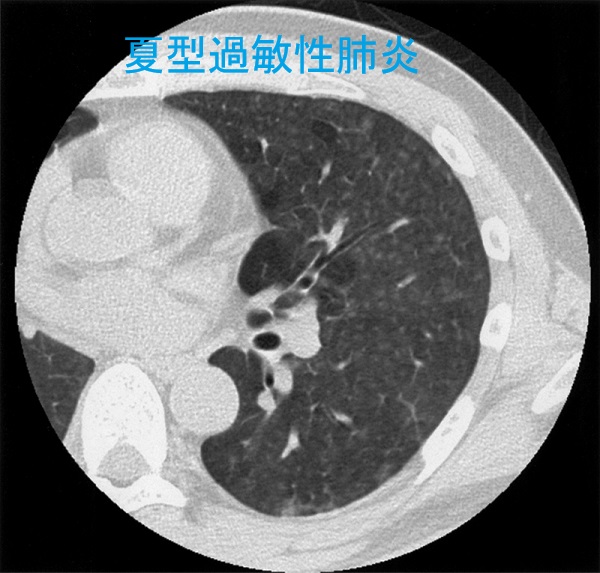

夏型過敏性肺炎

過敏性肺炎(免疫過敏性肉芽腫性肺炎)は、カビ、細菌、動物性蛋白、化学物質の反復吸入によって肺胞でおきるⅢ,Ⅳ型アレルギー反応です。

1. 夏型過敏性肺炎(75%):日当たり・風通しの悪い古い家屋で、高温多湿な夏にトリコスポロン(主にはトリコスポロン・アサヒ:Trichosporon asahii)というカビが繁殖するのが原因。特に土壁や観葉植物の土壌にトリコスポロンが繁殖しやすい。

6. 肺CTでは、

①小葉中心性にびまん性散在性小粒状陰影は甲状腺癌肺転と鑑別

②モザイク状の間質性陰影(すりガラス陰影)は橋本病に合併する間質性肺炎と鑑別

過敏性肺炎 胸部エックス線写真

両側下肺野にスリガラス影

過敏性肺炎 CT画像

両側肺野に小葉中心性粒状影